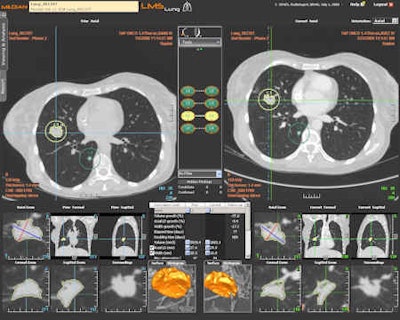

Follow-up of a pulmonary mass with the LMS platform (oncology imaging). Besides oncology imaging specialists, chest and abdominal radiologists will in the future use the software for pretreatment measurements after first detection of tumors. All images courtesy of Median Technologies.

Follow-up of a pulmonary mass with the LMS platform (oncology imaging). Besides oncology imaging specialists, chest and abdominal radiologists will in the future use the software for pretreatment measurements after first detection of tumors. All images courtesy of Median Technologies."LMS runs within PACS to find the same lesions at second examination follow-up, and measure and chart any changes. This saves the radiologist time; each follow-up CT evaluation process is 10 to 15 minutes faster than without using LMS," said Dr. Luis Martí-Bonmatí, La Fe's director of clinical imaging and president elect of the European Society of Gastrointestinal and Abdominal Radiology. "My feeling is that this automatic evaluation is more accurate and reliable as it doesn't suffer from interobserver variation."